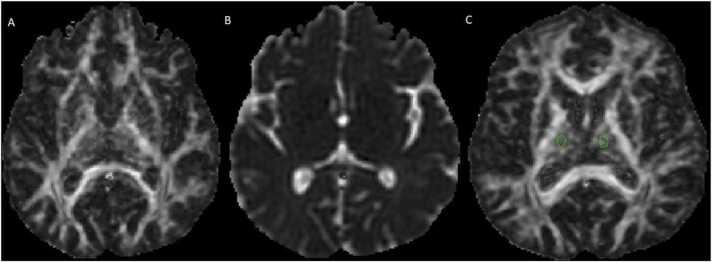

30 relapsing-remitting MS (RRMS) cases and 30 normal individuals were included. Conventional MRI (T2, FLAIR) was acquired to confirm NAGM in MS patients. A T1 MPRAGE protocol was used to normalize DTI images. FSL, SPM, and Explore DTI software were employed to reach Mean Diffusivities (MD), Axial Diffusivities (AD), Fractional anisotropy (FA), and Radial Diffusivity (RD) at the thalamus and the basal ganglia.

The FA and RD of the thalamus were decreased in healthy controls compared to MS cases (0.319 vs. 0.296 and 0.0009 vs. 0.0006, respectively) (P < 0.05). The AD value in the thalamus and the FA value in the caudate nucleus were significantly lower in MS cases than in controls (0.0009 vs. 0.0011 and 0.16 vs. 0.18, respectively) (P < 0.05). MD values in the thalamus or basal ganglia were not significantly different between groups.

DTI measures including FA, RD, and AD have a good diagnostic performance in detecting microstructural changes in the normal-appearing thalamus in cases with RRMS while they had no significant relationship with clinical signs in terms of EDSS.